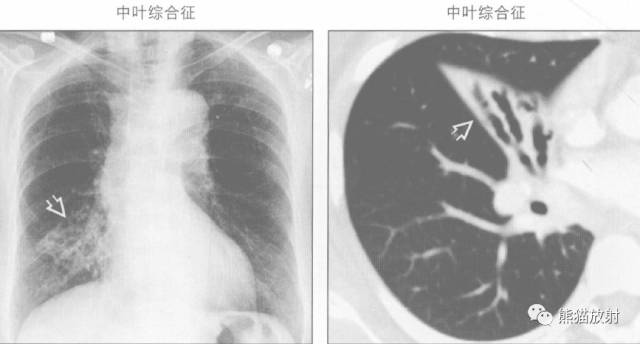

“右肺中叶综合征”的鉴别诊断